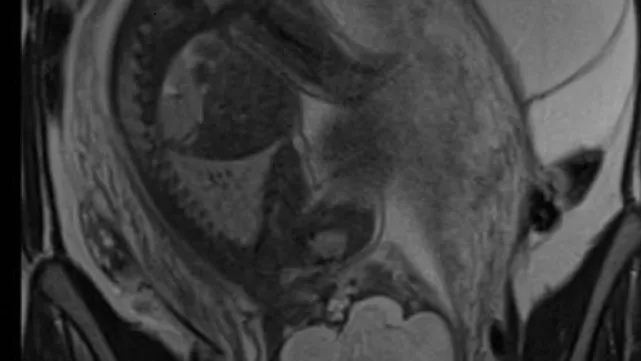

• 14h - IRM et kystes ovariens pendant la grossesse

Pre Isabelle Thomassin Naggara, Hôpital Tenon, Université Sorbonne, Paris